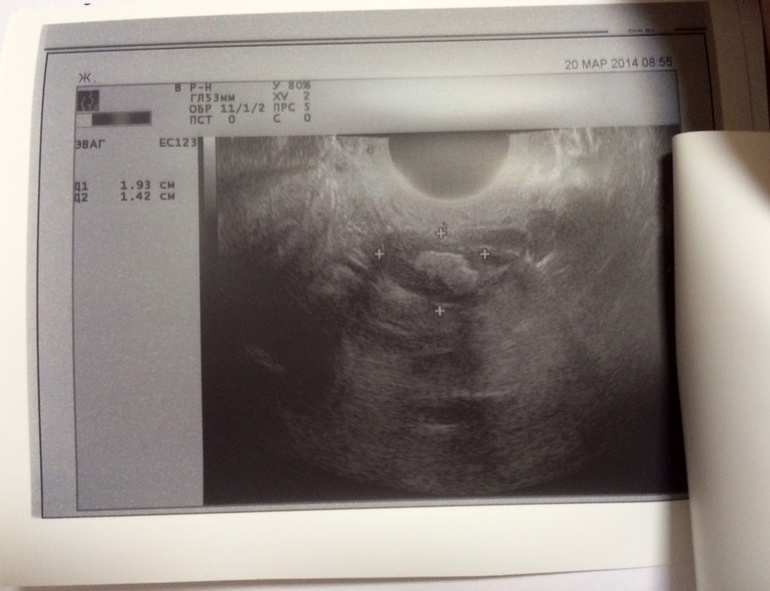

Посмотрите узи тот кто понимает ,

На картинке что ? Яйцо ? Или эмбрион ?

Вот, как я вам писала- первое фото ПЯ пустое и одно пока 6 мм и срок 5-6 нед, по узи поставили меньше срок на неделю! А второе фото через неделю (6-7 нед)уже с эмбрионом и всем прочим:

Плодное яйцо и желточный мешочек. ЖМ присутствует только в том случае, когда Б развивается иначе пропадает! Поэтому все у вас отлично, скоро и эмбриончик увидите!

На фото, матка, в ней ПЯ, эмбрион не вижу - очень далеко ПЯ поэтому не разглядеть. Но по моему виден желточный мешочек.